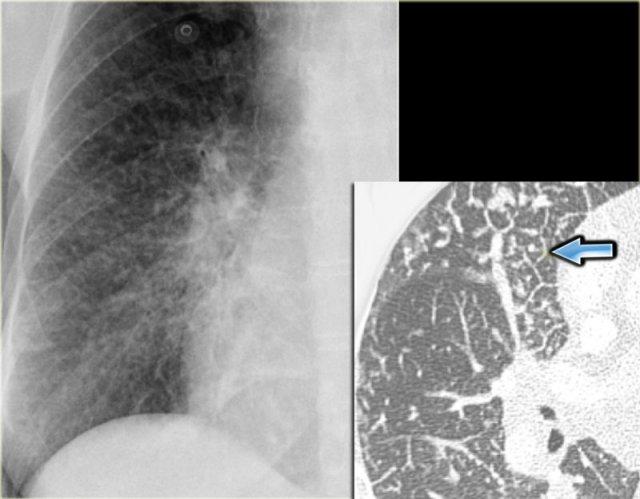

Đây là một phim X-quang ngực thẳng khác với phù mô kẽ và đường Kerley B ở bệnh nhân suy tim sung huyết.

CT cho thấy dày vách liên tiểu thùy.

Đôi khi hình ảnh dạng lưới thô hơn như trong trường hợp suy tim sung huyết này.